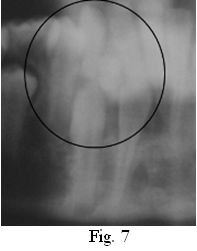

Al examen radiográfico se observa una lesión radiopaca, compuesta por varios dentículos, rodeada de una zona radiolúcida bien delimitada. Se diagnostica la presencia de un Odontoma Compuesto que representa una traba de erupción para los órganos dentarios 4.2 y 4.3 (Figs. 6 y 7).

Los odontomas compuestos son los tumores odontogénicos más frecuentes, relacionados con dientes permanentes retenidos. En este caso clínico, se presenta un odontoma compuesto de alrededor de 10 mm de diámetro, asintomático, en el sector anterior del maxilar inferior. Fue un hallazgo radiográfico indagando sobre la etiología de la ausencia de algunas piezas permanentes y el desplazamiento de otras, asociado a la persistencia de un diente caduco (8.3), lo que coincide con lo descrito por varios autores (7, 8, 11, 12, 17). En concordancia con la bibliografía consultada, los controles periódicos clínicos y radiográficos realizados a la paciente luego de la eliminación quirúrgica del odontoma, no muestran signos de recidiva (3, 12, 23, 26).